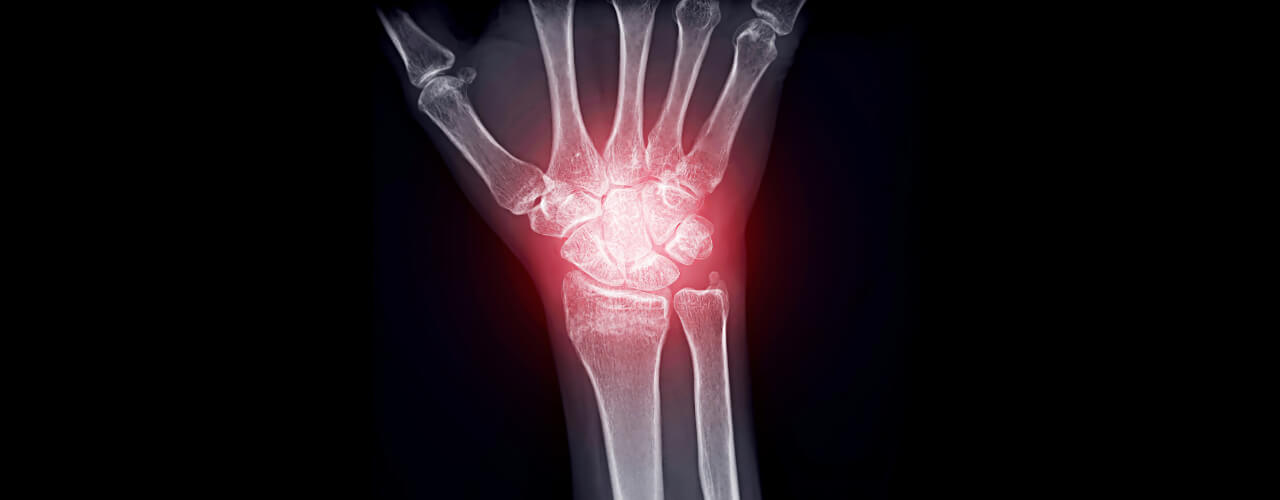

Linda’s arthritis had progressed over the years, making simple tasks like opening jars or climbing stairs feel monumental. The swelling in her knees and hands made her joints stiff and sore, and the pain seemed to flare up unpredictably.

Over time, Linda noticed remarkable improvements. The swelling in her knees reduced significantly, and her hands felt less stiff. Tasks that once seemed impossible, like kneeling in the garden or holding pruning shears, became enjoyable again.